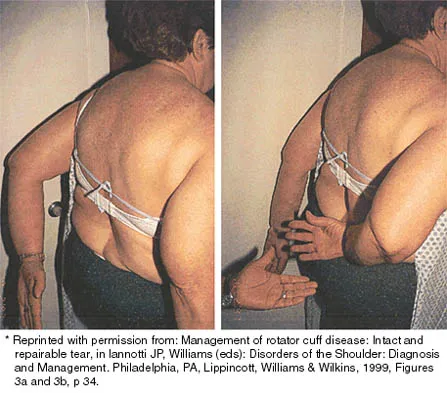

Examination of the shoulder seen in Figure 52 shows atrophy and tenderness of the infraspinous fossa and profound weakness in external rotation. The supraspinous fossa shows normal muscle bulk. What is the most likely cause of this condition?

Compression of the suprascapular nerve by a ganglion cyst is a well-documented cause of pain and weakness in the shoulder. Isolated involvement of the infraspinatus indicates that the area of entrapment is at the spinoglenoid notch and not the suprascapular notch. The majority of ganglion cysts found in the shoulder are related to tears of the labrum. When such a compressive lesion is found, decompression can be accomplished through either an open or arthroscopic approach. Several authors have shown the value of arthroscopy in the treatment of this condition. It has been shown that it is technically possible to decompress a paralabral ganglion cyst using arthroscopy; this method is usually followed by repair of the torn labrum. Alternatively, arthroscopic repair of the labrum can be performed and the cyst may be aspirated at the time of surgery. Open cyst excision through a posterior approach is also an acceptable method of treatment. Schickendantz MS, Ho CP: Suprascapular nerve compression by a ganglion cyst: Diagnosis by magnetic resonance imaging. J Shoulder Elbow Surg 1993;2:110-114. Thompson RC, Schneider W, Kennedy T: Entrapment neuropathy of the inferior branch of the suprascapular nerve by ganglia. Clin Orthop 1982;166:185-187.